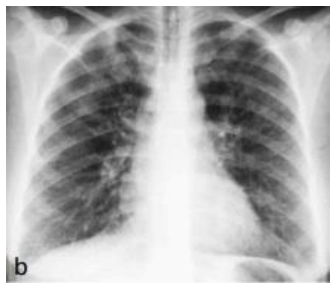

Analise a imagem abaixo para responder à questão.

É correto afirmar que a radiografia acima demonstra